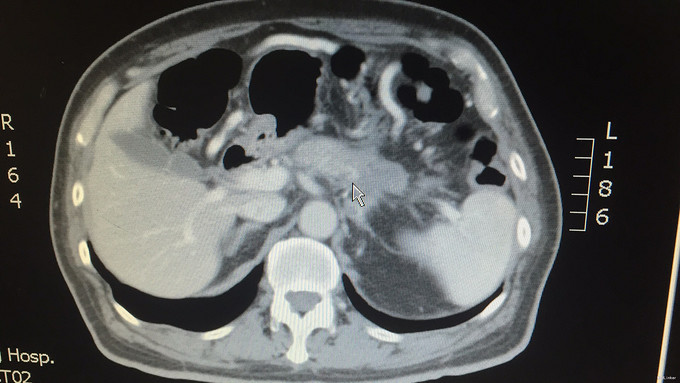

查体:腹部平坦,未见腹壁紧张及腹壁静脉曲张,无肠型及蠕动波;腹平软,无压痛、反跳痛、肌紧张等,未及明显异常,肝区无叩击痛,移动性浊音(—),肠鸣音4次/分,无增强或减弱。振水音(+)。 辅查:外院血癌胚抗原:41.39ng/ml;外院上腹部MRI增强:胰腺体尾部占位,考虑恶性,胰腺癌可能性大。我院上腹部CT平扫+增强:胰腺体部以远前后径约2.6cm,平扫CT值约50HU,增强后动脉期及门脉期CT值约68HU。胰胃间隙及胰后间隙稍模糊,可见数个淋巴结影,最大者长径约9.2cm。左侧肾上腺后支稍饱满,似可见一长径约1cm稍高密度影。[印象]:1.胰腺体尾部占位,恶性可能;2.腹腔内及腹膜后数个淋巴结;3.左侧肾上腺饱满,清结合临床。我院肿瘤指标检查:CA19-9:4.13U/ml,CEA:34.91U/ml,AFP:5.40U/ml。